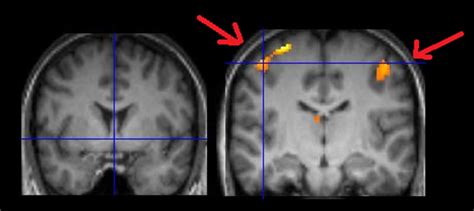

Le tecniche di neuroimaging, in particolare, hanno rivoluzionato lo studio del cervello. La tomografia computerizzata (TAC) e la risonanza magnetica (RM) strutturale sono essenziali per identificare lesioni e anomalie anatomiche. Tuttavia, sono le tecniche di neuroimaging funzionale, come la risonanza magnetica funzionale (fMRI), la tomografia ad emissione di positroni (PET) e la tomografia ad emissione di fotone singolo (SPECT), a offrire una finestra sull'attività cerebrale in tempo reale. Queste tecniche permettono di ottenere una rappresentazione dell'attivazione di specifiche aree cerebrali durante l'esecuzione di determinati compiti cognitivi, sia in soggetti sani che in pazienti con lesioni cerebrali.